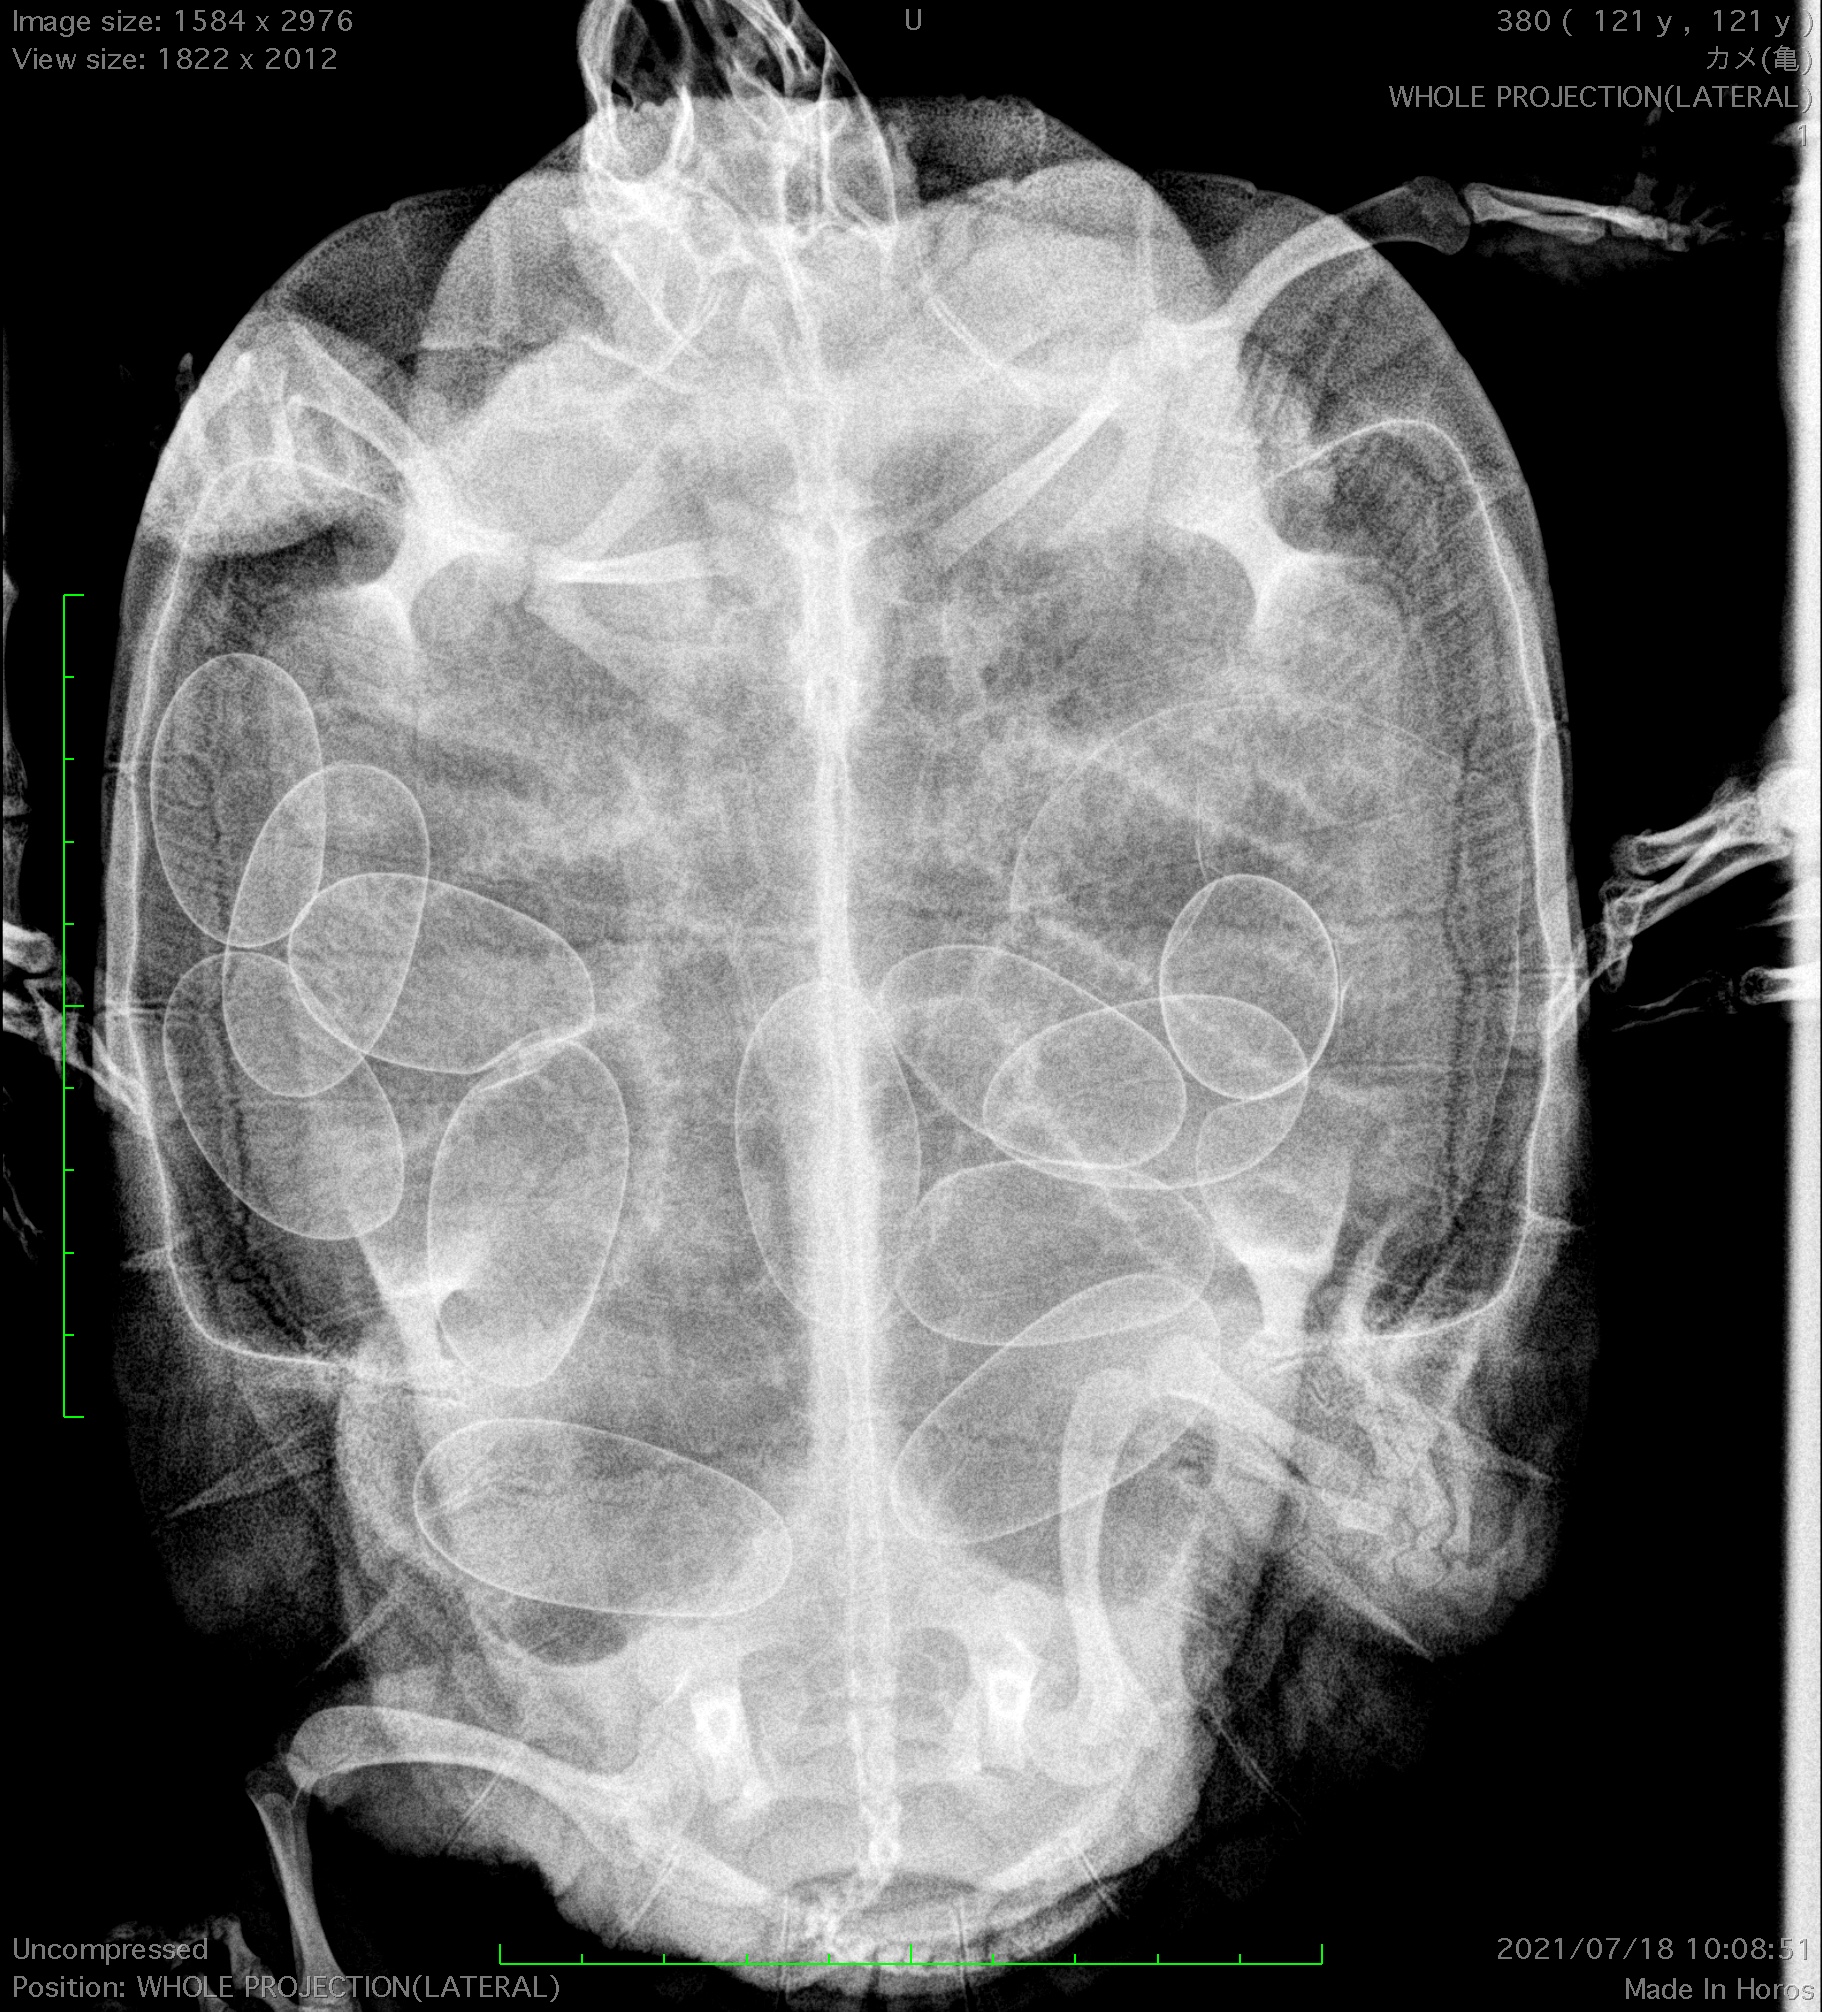

キキ動物病院 住所 大阪府堺市中区深井北町1173 電話番号 電話可能時間9:30~21:00 HP https//kikipetcliniccom/ 亀の卵づまり 卵巣卵管摘出 亀、特にミズガメといわれる クサガメ アカミミガメなどの仲間は よく食欲がない、なんか元気ない といわれて来院してきます。 色んな原因がありますが

21/3/22 じつれぷ ミドリガメの卵詰まりが起きました! 卵詰まりについて うちで飼っているミドリガメが卵詰まりを起こしました。 体の中で、卵が詰まってしまうと死んでしまうこともあ18/6/17 カメの卵詰まりは、 食欲減退、排便減少、水ガメに多く見られ、卵が巨大だったり変形などの異常、カルシウムなどの栄養不足でなってしまう ということです。 (カルシウムの強化は、/2/16 更新日: 公開日: 爬虫類 Tweet 夏、飼っているメスのミドリガメが急に食欲がなくなり、急に暴れるみたいに激しく動き回り始めたら、それは産卵のサイ

8/4/14 卵があるようだが、産まず、元気もなくなってきた 卵詰まり、卵閉塞という病気の可能性があります。 うまく卵が排出されず、詰まってしまうのです。 治療としては、注射で促進剤をLos últimos tweets de @kasumi_plants3,315 views 亀の卵詰まり 症状と対処法や手術(産卵失敗,動かない,食欲不振,食べない,後ろ足を引きずる大阪堺 爬虫類 亀の病院 more more Like Dislike Share Save キキ動物病

この病気は、飼育ケース内に雄がいない環境であっても起こり得るので注意が必要です。(この場合の卵は「無精卵」です) その2 卵詰まりの原因と症状 卵詰まりの原因としては、卵をじつれぷ idjiturep ミドリガメの卵詰まりが起きました! 卵詰まりについて うちで飼っているミドリガメが卵詰まりを起こしました。 体の中で、卵が詰まってしまうと死んでしまうこともあり